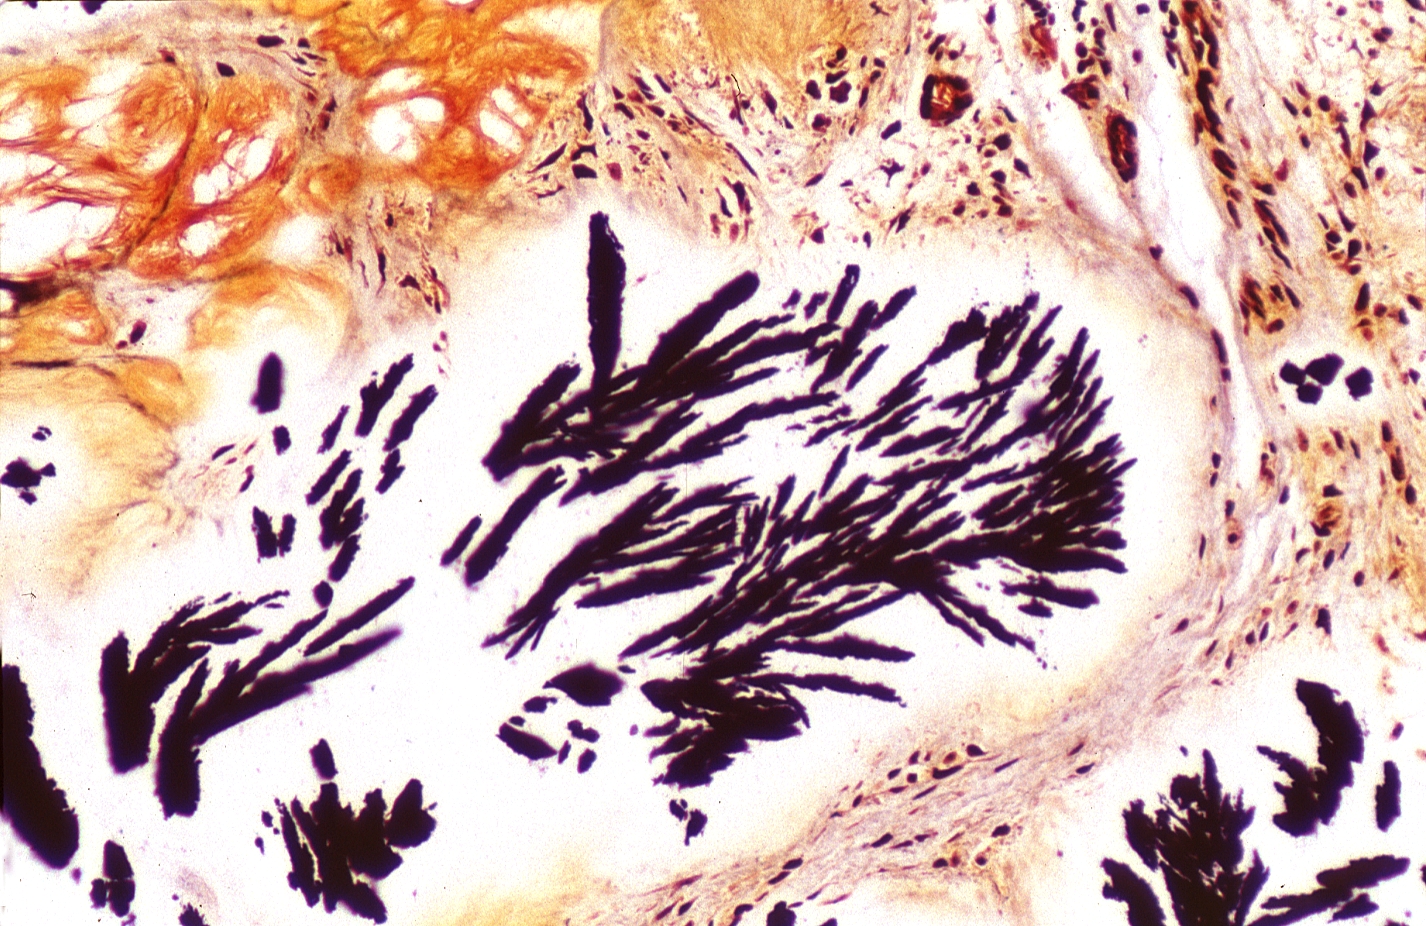

HISTOLOGY: MUSCULOSKELETAL: BONES: JOINTS: Gout, alcohol fixed tissues, monosodium urate crystals